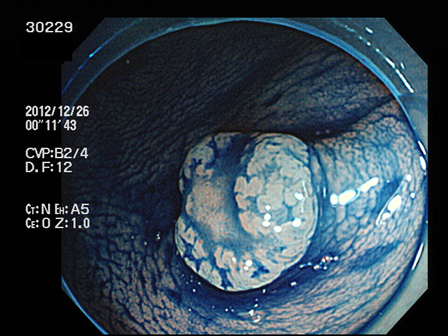

上記100名より抽出した平坦・陥凹型腺腫(=癌化の危険が高いが見落としやすい病変)の内視鏡写真